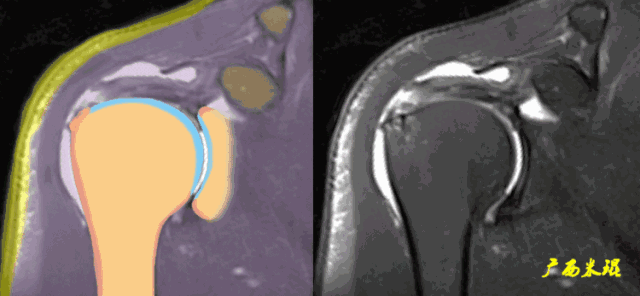

(1)斜冠状位:平行于冈上肌腱长轴,主要评估冈上肌。

正常肩袖的MRI表现

各个序列肩袖均表现为均匀的低信号,是肌腱的延续。

肩袖损伤的MRI分级(Zlaikin)

Grade0:肩袖形态正常,连续性完好,肩袖信号正常。

Grade1:肩袖形态正常,连续性完好,肩袖内信号异常。

Grade2:肩袖连续性存在,形态异常(肩袖变薄/变厚,形态不规则)。

Grade3:肩袖外形异常,连续性中断。

在Zlaikin分级中,0级是正常肩袖,1、2级代表退变,3级为撕裂,也就是真正的肩袖损伤。

肩袖撕裂的MRI表现

(1)信号异常

肩袖出现3级信号,是诊断的直接征象,一旦发现3级信号,肩袖撕裂无疑。